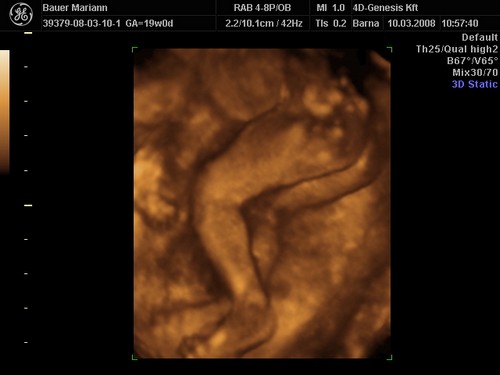

Bence 18 hetesen